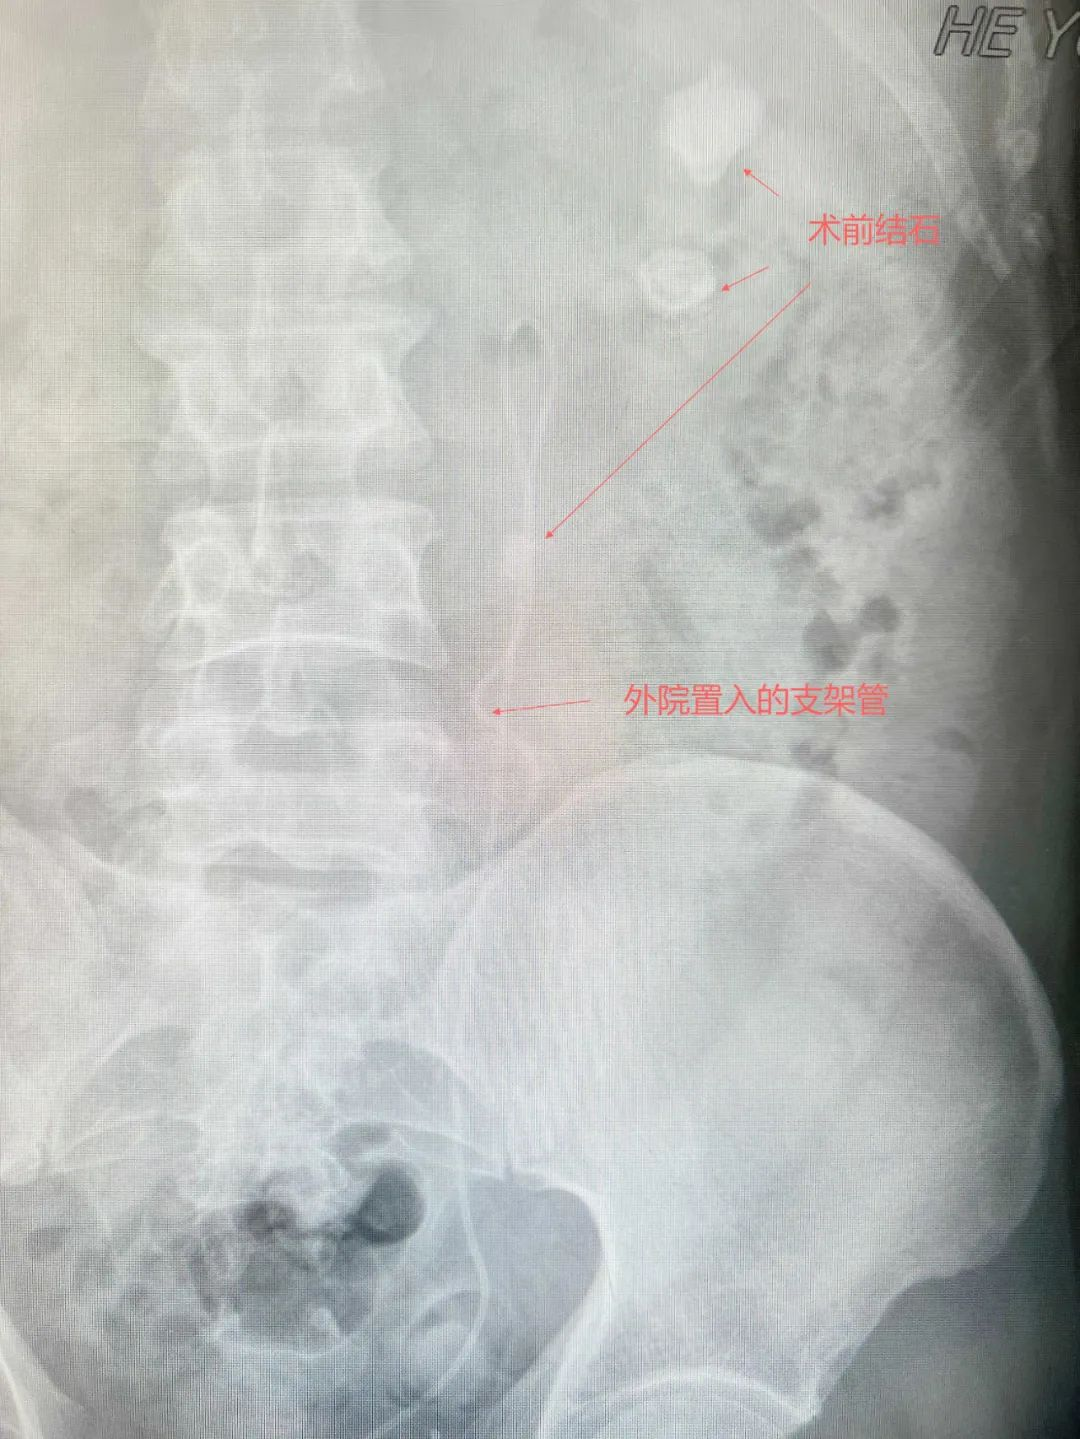

▲术前腹平片

多年病痛反复折磨,跨省求医重燃希望

向先生患有左肾多发结石多年,曾在四川当地医院接受多次开放式手术和输尿管镜手术,但结石残留问题始终反复,未能彻底解决,最大残留结石直径达5厘米。更为凶险的是,结石频繁脱落引发输尿管梗阻,导致多次感染性休克,曾到ICU抢救。即便在四川某顶级三甲医院,专家也摇头叹息:“肾脏结构复杂如迷宫,常规手段已无能为力”。就在向先生近乎绝望时,他偶然得知广东省人民医院泌尿外科专家毕学成主任正在我院开展帮扶工作,当即决定跨越1600公里,从四川乘飞机辗转至广州,再转车奔赴河源。